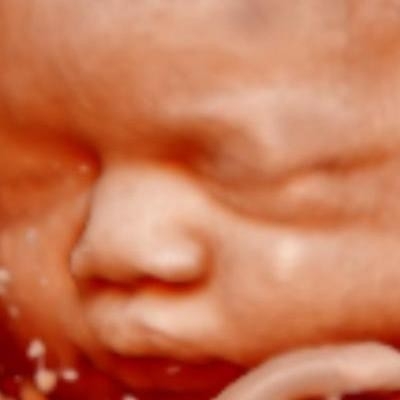

En Policlínica Meprysa creemos y apostamos por una Medicina Personalizada, integral y moderna, con extraordinarias ventajas que garantiza a nuestros pacientes una atención más segura y más eficiente. Ecografía 4D, donde se puede ver al bebé en movimiento, se entrega un CD con fotografías y videos. Las ecografías se realizan hasta la semana 30 del embarazo

Ecografía 4D, donde se puede ver al bebé en movimiento, se entrega un CD con fotografías y videos. Las ecografías se realizan hasta la semana 30 del embarazo